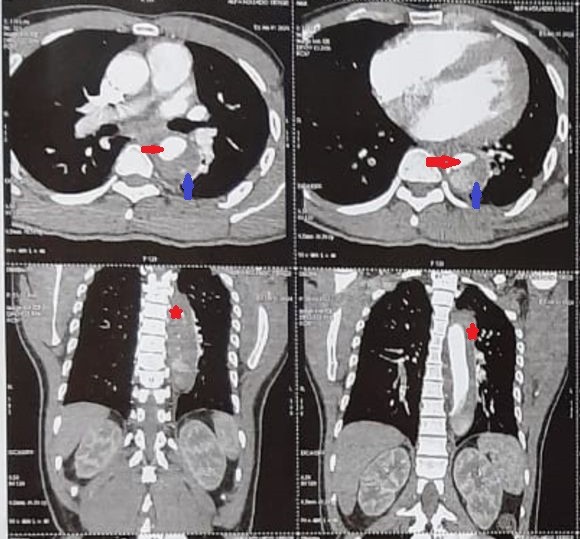

Figure 1: Angioscanner Thoracique en coupe axiale montrant l’aorte thoracique descendante disséquée avec le vrai chenal( flèche rouge) et le faux chenal non circulant(flèche bleu). Coupes frontales montrant l’aorte thoracique descendante disséquée (étoiles rouges).

Nous rapportons le cas d’un patient de 35 ans, sans facteur de risque cardiovasculaire, qui a été référé aux urgences de l'Institut de cardiologie d'Abidjan (ICA) pour une dissection aortique type B de Stanford confirmée par un angioscanner thoraco abdominal. L’anamnèse a révélé un début des symptômes, remontant à deux semaines avant l’admission et marqué par une douleur thoracique d'installation brutale, transfixiante, irradiant aux lombes. Une sensation de faiblesse des membres inférieurs est apparue 2 jours plus tard, associée à une rétention d'urine. Une dizaine de jours après le début des symptômes, le patient a consulté d’abord dans un centre de santé où il est réalisé une IRM dorso-lombaire. Cette imagerie a mis en évidence, en séquence T2, un hypersignal focal au niveau de la moelle épinière avec un niveau de T5 à L1 traduisant une ischémie médullaire. De plus, l’IRM a retrouvé une dilatation de l’aorte thoracique descendante avec une image suspecte de dissection aortique. Un angioscanner a été alors réalisé et a confirmé le diagnostic de dissection aortique type B de Stanford. A l’admission aux urgences de l’ICA, deux semaines après le début des symptômes, l'examen clinique a révélé une morphologie longiligne avec un rétrognathisme, une hyperlaxité articulaire et des pieds plats. Ces signes ont fait suspecter un trouble du tissu conjonctif, éventuellement un syndrome de Marfan, alors que le patient ne présentait aucun facteur de risque cardiovasculaire connu. On notait également une hypertension artérielle grade 1, une paraplégie totale flasque avec une force musculaire cotée à 0 sur 5 aux 2 membres inférieurs ainsi qu’une hypoesthésie cutanée et une atonie du sphincter anal au toucher rectal. Un échodoppler cardiaque réalisé a retrouvé une aorte initiale de taille normale avec un diamètre de l’aorte au niveau du sinus à 34mm, à la jonction sino-tubulaire à 32 mm, une absence de fuite valvulaire et des cavités cardiaques de taille normale. A l’echodoppler, l’aorte abdominale ne présentait pas de dilatation anévrismale avec un diamètre antéro postérieur à 24 mm dans sa portion sous rénale. On visualisait une image de flap intimal. Au vu du long délai de 12 jours entre l’installation de la paraplégie et l’admission aux urgences et devant l’examen neurologique, il a été conclu à un état de myélomalacie. Devant ce tableau de dissection aortique type B de Stanford compliqué d’ischémie médullaire, un traitement endovasculaire a été indiqué. Dans l'attente de la prise en charge interventionnelle, le patient a reçu un traitement médical à base d'antalgiques et d'antihypertenseurs. Cependant, avant la réalisation du traitement endovasculaire, son état clinique s’est détérioré avec l’installation d’un état de choc, environ vingt-quatre heures après son admission. Le patient est décédé dans un tableau de choc hémorragique.